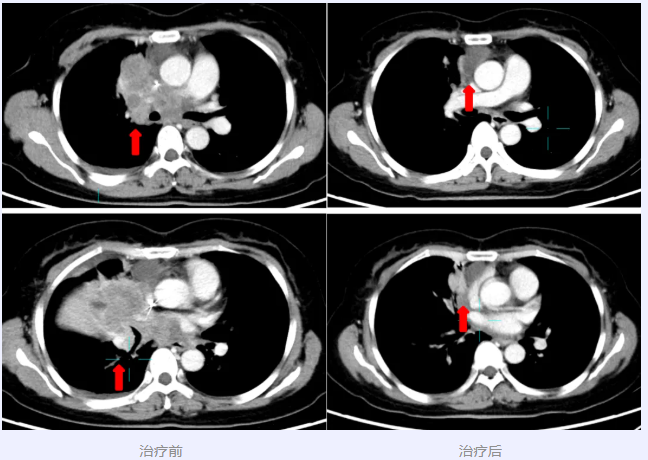

近日,我院胸部肿瘤内科专家团队通过前沿临床研究药物精准干预,成功治疗一位晚期肺鳞癌患者,肿瘤病灶实现明显退缩。

林动主任医师团队接诊后,经全面评估,患者符合入组条件,成功加入“注射用SKB445治疗晚期实体瘤受试者的安全性、耐受性、药代动力学和抗肿瘤活性的Ⅰ期临床研究”,用药1周期后肿瘤即得到明显控制,疗效评估大PR(部分缓解)。

林动主任医师介绍,临床研究不是“最后一试”,而是为晚期患者提供前沿治疗的重要途径。该例为难治性肺鳞癌,标准治疗失败后肿瘤快速进展。SKB445作为一种针对CDH3靶点的新型ADC药物,通过靶向特定抗原递送强效细胞毒素精准杀伤肿瘤细胞,兼具靶向性与高效低毒的特点。入组用药1周期疗效即达大PR,体现了创新药物潜在突破性疗效。期待更多患者通过科学探索,获得新生机。